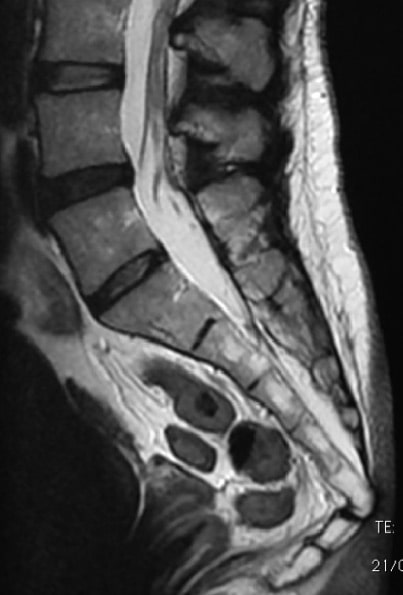

Es tracta de la luxació que menys s’acostuma a diagnosticar mitjançant proves complementàries, perquè les RX i RMN que es realitzen en la columna completa o fins i tot a la zona lumbosacra per altres quadres o sospites, no arriben a visualitzar el còccix a partir de la vèrtebra S2 cap avall, i encara que s’efectuïn fins al final del còccix, a aquest nivell pot ser difícil detectar la separació mitjançant la imatge radiològica, i sigui necessari un TAC o una RM.